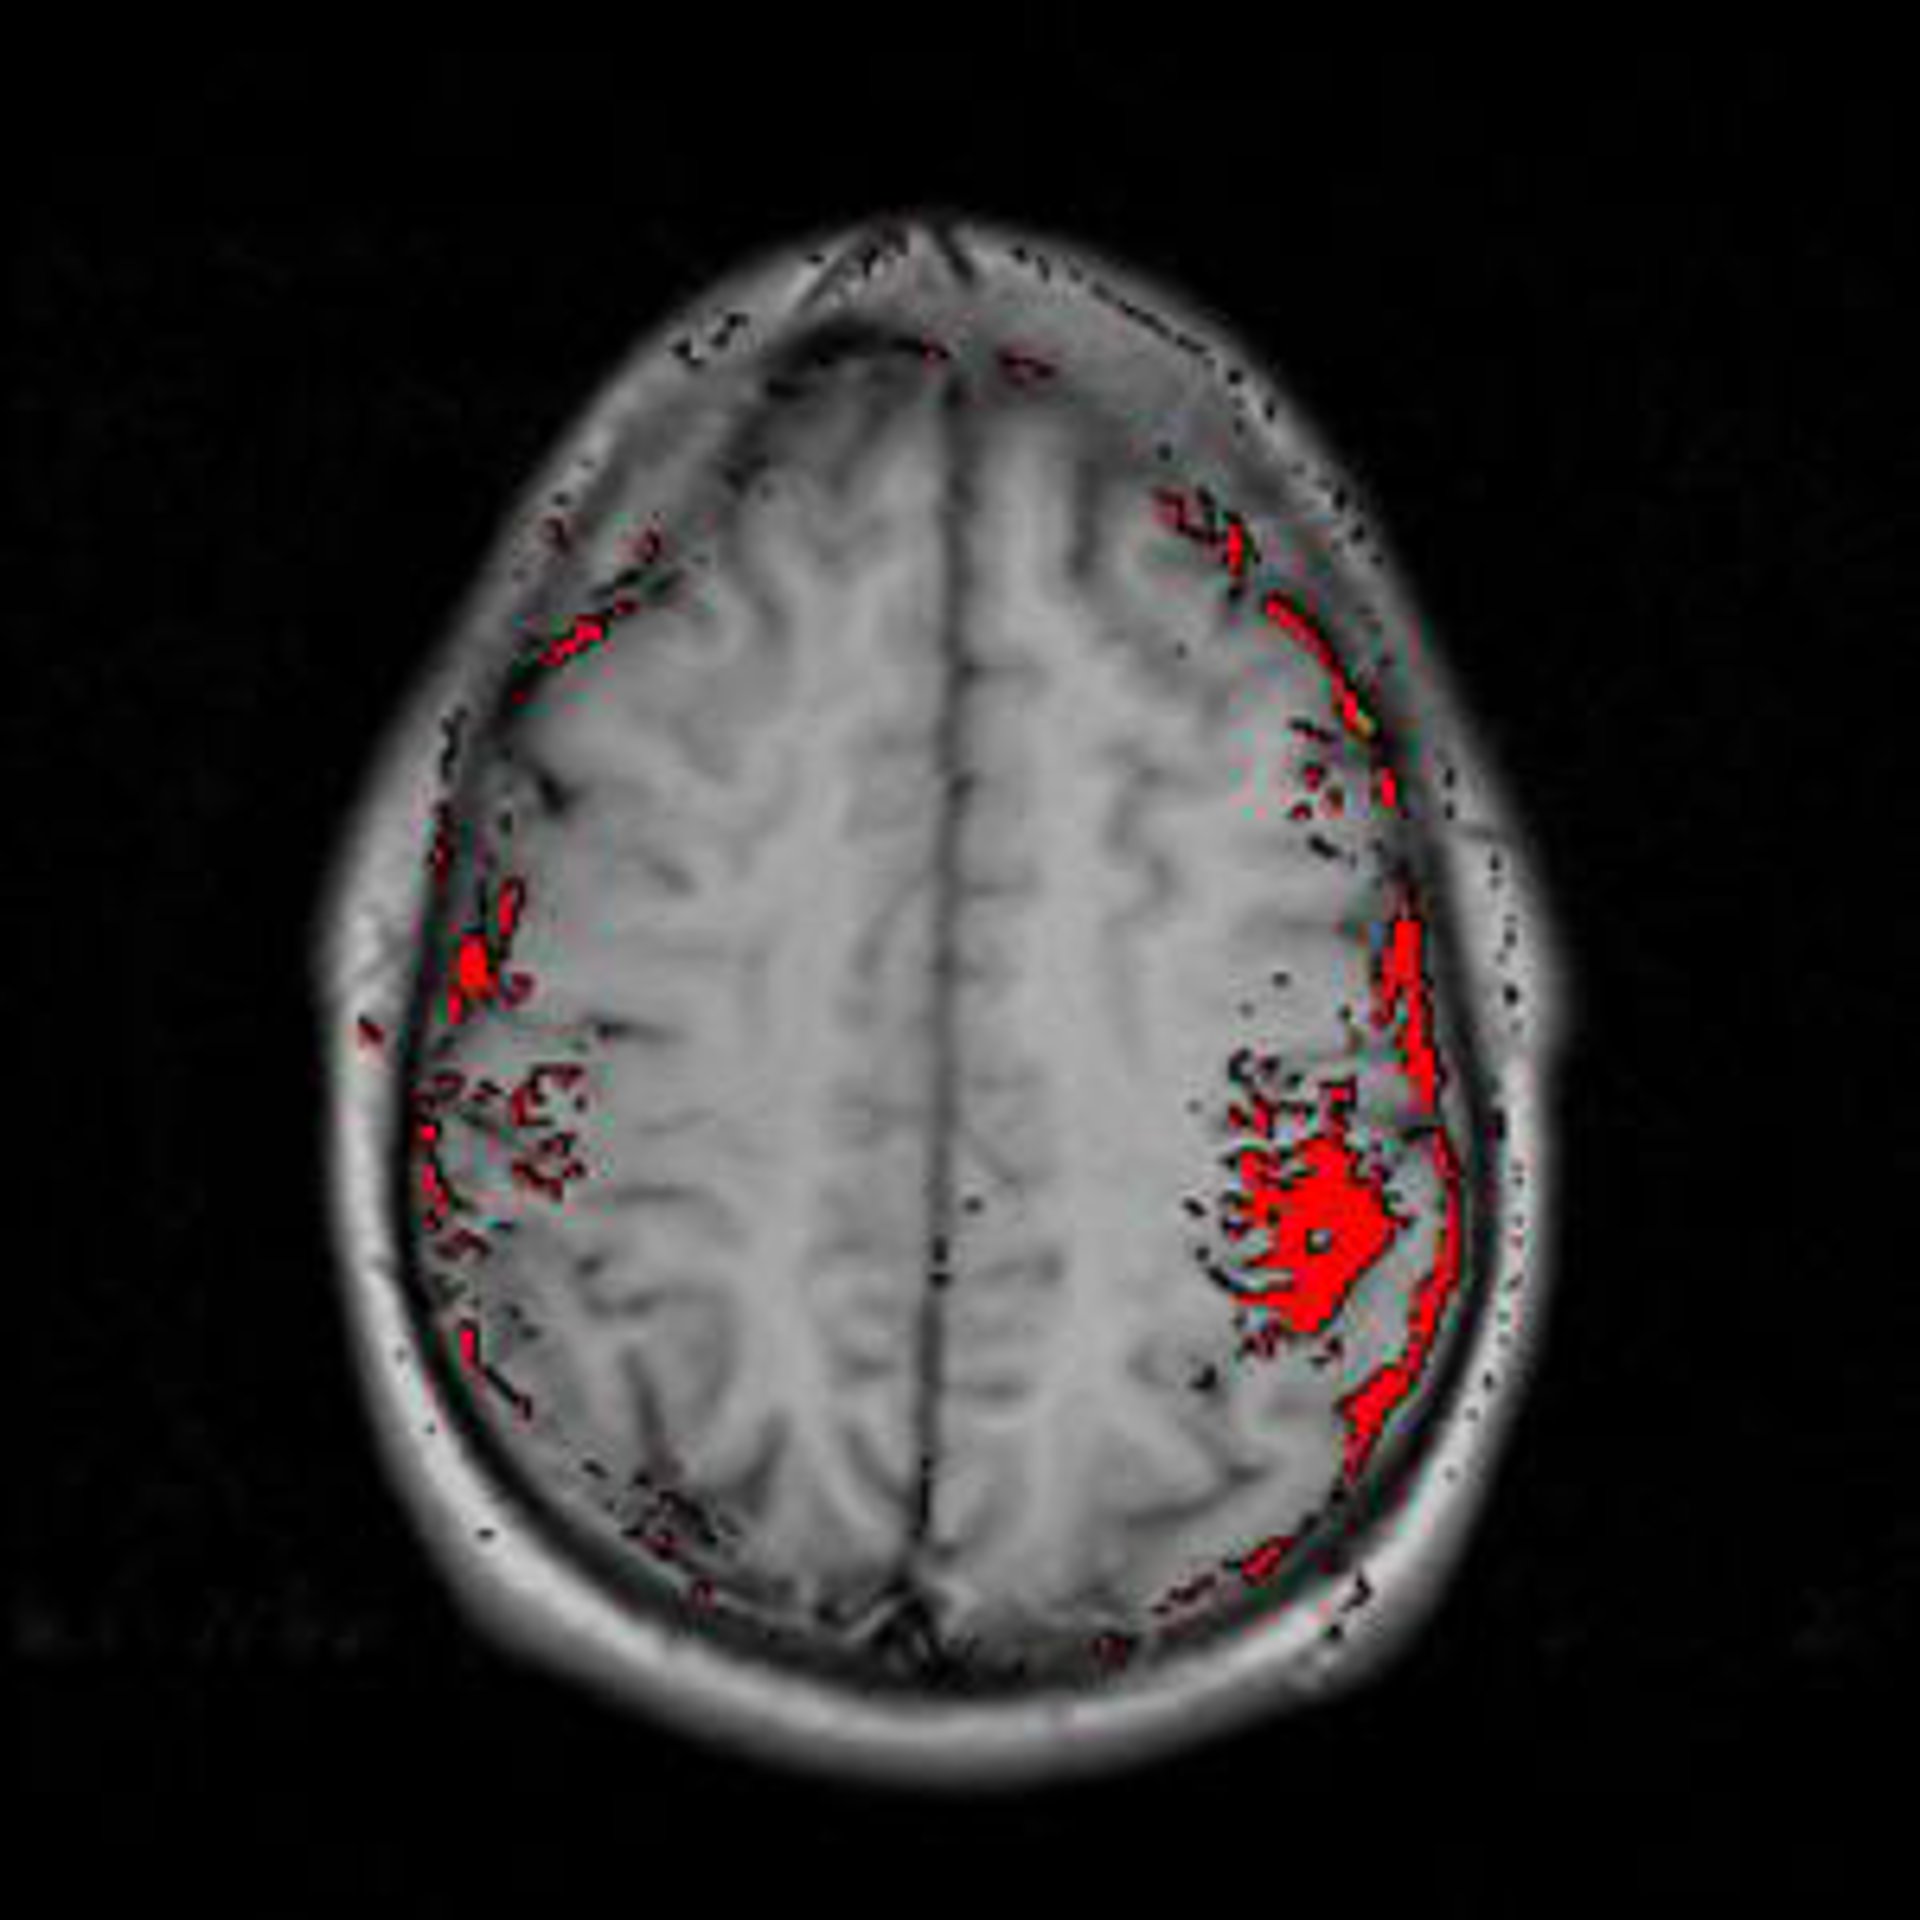

Radiografía cerebro con signos de infarto